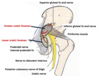

Anterior Triangle Borders

- roof- investing fascia & platysma

- superior- inferior border of the mandible

- anterior- median line of the neck

- posterior- anterior border of SCM

- Floor-prevertebral fascia

Anterior Triangle Contents

- muscular triangle: infrahyoid muscles, thyroid & parathyroid glands

- carotid triangle:common carotid a., internal jugular v., portions of last 3 cranial nerves

- digastric triangle: submandibular gland, facial artery, internal carotid a., internal jugular v., CN IX, CN X

Posterior Triangle Borders

- roof- fascia & platysma

- anterior- posterior border of SCM

- posterior- anterior border of trapezius muscle

- inferior- superficial aspect middle 1/3 of clavicle

- floor- prevertebral fascia

Posterior Triangle Contents

- transverse cervical a.

- CN XI

- upper trunk of brachial plexus

- subclavian a.

- dorsal scapular n.

- long thoracic n.

- n. to subclavius

- suprascapular a. & n.